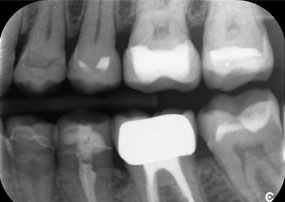

El reto consistía en extraer doce coronas bloqueadas con aleación común sin dañar los raigones subyacentes. Se utilizó el contra-ángulo para realizar incisiones precisas en las capas de cerámica y separar las estructuras metálicas con una fresa de metal duro, con el fin de extraer las coronas con un traumatismo mínimo. En solo 30 minutos se retiraron las coronas antiguas y se pudo preparar el nuevo trabajo, compuesto por zirconio completo en la zona posterior y coronas con recubrimiento en la zona anterior. El resultado fue una reconstrucción completa, satisfactoria tanto desde el punto de vista funcional como estético (véase la fig. 1).